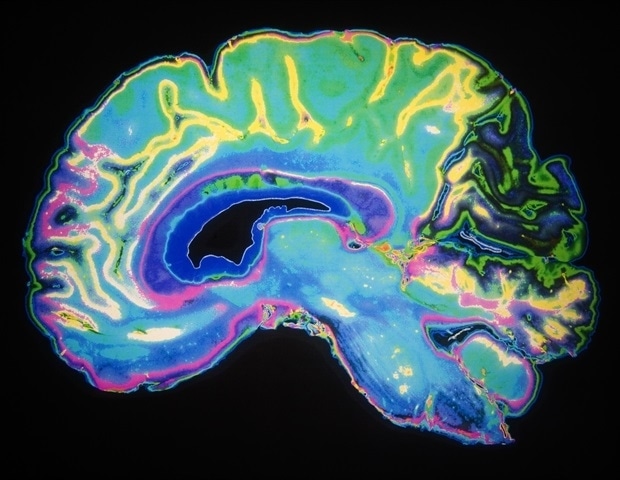

Η μάθηση ενισχύει τη συντονισμένη δράση των αισθητηριακών νευρώνων στον εγκέφαλο

Όταν βελτιώνετε μια ικανότητα, όπως το να αναγνωρίζετε ένα οικείο πρόσωπο σε ένα πλήθος ή να εντοπίζετε ένα τυπογραφικό λάθος με μια ματιά, οι αισθητηριακοί νευρώνες στον εγκέφαλό σας γίνονται πιο συντονισμένοι. Αντί να δρουν ανεξάρτητα, μοιράζονται πληροφορίες, όπως αποκαλύπτει μια νέα μελέτη από ερευνητές του Πανεπιστημίου της Ρότσεστερ και του Ινστιτούτου Νευροεπιστήμης Del Monte, που δημοσιεύθηκε στο περιοδικό Science. Αυτή η ανακάλυψη αμφισβητεί μια μακροχρόνια υπόθεση στη νευροεπιστήμη, σύμφωνα με την οποία η μάθηση βελτιώνει την αποτελεσματικότητα μειώνοντας την επανάληψη των νευρωνικών σημάτων.